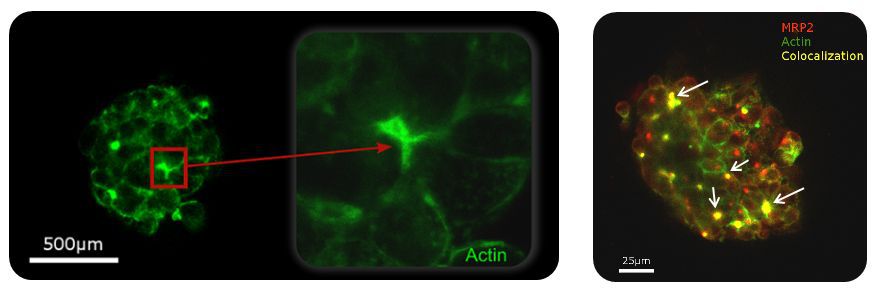

Maintains hepatocytes functions: Biliary Canaliculi Formation – HepG2

Formation of canaliculi network with Actin and MRP2 colocalization